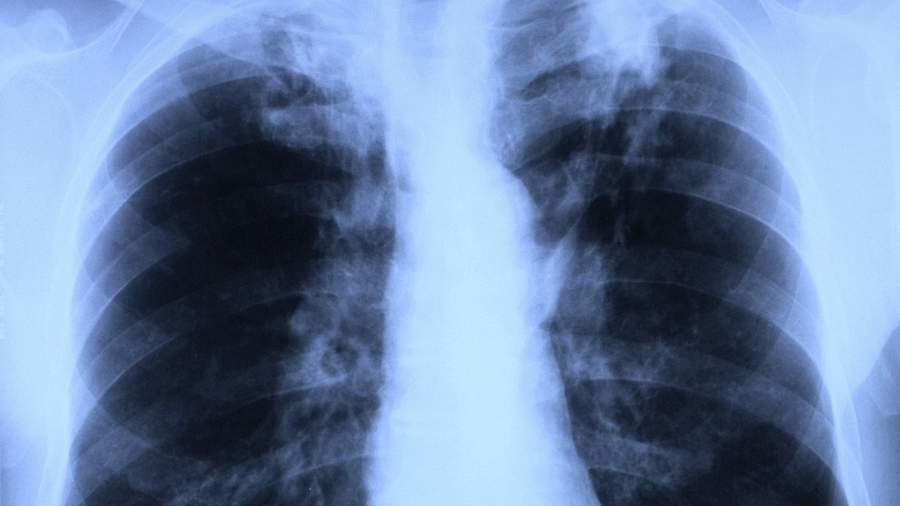

В Подмосковье сообщили о снижении на 20% заболеваемости туберкулезом

Фото: Global Look Press/Ernst-Georg Kohout/imagebroker

Заболеваемость туберкулезом в Подмосковье снизилась в 2020 году на 20%. Об этом в понедельник, 15 марта, сообщили в пресс-службе министерства здравоохранения Московской области.

«Заболеваемость туберкулезом в Московской области снизилась на 20% в 2020 году по сравнению с 2019 годом. По итогам 2020 года число впервые выявленных больных туберкулезом на территории Подмосковья составило 1 тыс. 523 человека — на 357 меньше, чем в 2019 году», — цитирует сообщение агентство городских новостей «Москва».

Главный внештатный специалист-фтизиатр региона Сергей Смердин отметил, что значительно снизилось общее количество больных туберкулезом.

«В Московской области все пациенты обеспечены необходимыми противотуберкулезными препаратами и более 80% пациентов полностью излечились от туберкулеза в 2020 году», — рассказал эксперт.

Также в пресс-службе ведомства напомнили, что в Подмосковье работает Центр госпитализации больных туберкулезом, позволяющий контролировать госпитализацию пациентов в профильные отделения медицинских организаций на территории всего региона.

Ранее, 8 февраля, в Минздраве предупредили, что пациенты, которые переболели коронавирусом, имеют повышенный риск развития туберкулеза.

В связи с этим на начальном этапе ведения больного с подозрением на коронавирус следует обследовать его и на туберкулез, чтобы предупредить развитие сочетанной патологии, следует из десятой версии рекомендаций ведомства по профилактике, диагностике и лечению COVID-19, сообщает телеканал «360».